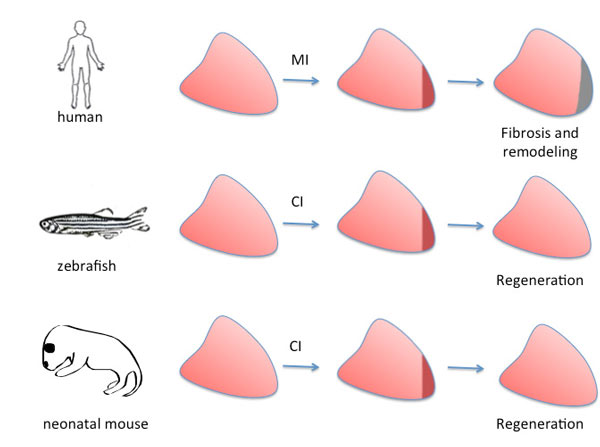

আর সেই সম্ভাবনাটা বেশ জোরালো ভাবেই উস্কে দিয়েছে একেবারে হালের একটি সাড়াজাগানো গবেষণার ফলাফল। ওই গবেষণা জানাচ্ছে, আমাদের মতো স্তন্যপায়ীদের হার্ট বা হৃদযন্ত্র হয়তো এক দিন তার নষ্ট হয়ে বা পচন ধরে যাওয়া কোষ, কলাগুলিকে নিজেই ‘বাতিল’ করে দেবে। তাদের জায়গায় বানিয়ে ফেলবে নতুন নতুন তরতাজা কোষ, কলা। যাকে জীববিজ্ঞানের পরিভাষায় বলে, ‘রিজেনারেশন’।

ওই ‘রিজেনারেশন’ পদ্ধতিতে আমাদের মতো স্তন্যপায়ীদের হার্ট এক দিন শরীরের ভেতরেই পুরনো নষ্ট হয়ে বা পচন ধরে যাওয়া কোষ, কলাগুলিকে ‘বাতিল’ করে দিয়ে তাদের জায়গায় নতুন নতুন কোষ, কলাগুলিকে একেবারে স্বাভাবিক নিয়মেই গায়ে-গতরে বাড়িয়ে তুলতে পারবে। একেবারে স্বাভাবিক নিয়মেই সেই কোষ, কলাগুলিকে হার্টে ছড়িয়ে দিতে পারবে। তাদের সুস্থ, সবল রাখার জন্য যা যা করণীয়, সেই সব কিছুই করতে পারবে। নিজেকে বাঁচিয়ে রাখা, সচল, সবল, সুস্থ রাখার জন্য হার্ট যদি প্রয়োজনীয় কাজগুলি আপনাআপনিই করে ফেলতে পারে, তা হলে আর তাকে ঠিকঠাক ভাবে চালিয়ে নিয়ে যাওয়ার জন্য বাইরে থেকে পেসমেকার বসাতে হবে কেন? কেনই-বা অ্যাঞ্জিওপ্ল্যাস্টির মতো হার্টে করতে হবে হরেক রকমের সুজটিল অস্ত্রোপচার? কেনই-বা প্রয়োজন হবে কার্ডিও-থোরাসিক সার্জারির?

আমাদের মতো স্তন্যপায়ীদের অনেক ‘পশ্চাতে’ বা পিছনের সারিতে রয়েছে জেব্রাফিশ। ঘটনা হল, স্তন্যপায়ীদের চেয়ে ‘জীবনের জটিলতা’য় অনেক অনেক পিছিয়ে থাকা এই জেব্রাফিশের মতো আরও অনেক প্রাণীই জীবনের এই মহা-মন্ত্রটা জানে। মানে, ‘রিজেনারেশন’টা করতে পারে, জানে। নষ্ট হয়ে যাওয়া বা পচন ধরে যাওয়া কোষগুলিকে বাতিল করে দিয়ে শরীরের ভেতরে তারা একেবারে প্রাকৃতিক নিয়মে আপনাআপনিই তৈরি করে নিতে পারে নতুন নতুন তরতাজা কোষ, কলা। বানিয়ে নিতে পারে নতুন নতুন অঙ্গ-প্রত্যঙ্গ। এটাই তাদের ‘রিজেনারেশন’ পদ্ধতি। ফলে তাদের শরীরে বাইরে থেকে কোনও সার্জারি, অপারেশনের প্রয়োজন হয় না। তাদের কোনও বিকল বা দুর্বল অঙ্গ-প্রত্যঙ্গ কেটে বাদ দিতে হয় না। কোনও অঙ্গ-প্রত্যঙ্গ প্রতিস্থাপনের দরকারও হয় না তাদের। আর এ ব্যাপারে আমরা মানুষ একেবারেই হতভাগ্য! ভাবুন, ঈশ্বর আমাদের এত কিছু দিয়েও কত কিছু, কত বড় একটা জিনিস আমাদের দেননি! শুধু মানুষই নয়, হতভাগ্য গোটা স্তন্যপায়ী কূল! তাদের কারও হাতেই নেই শত্রু-বধের এই অমোঘ অস্ত্র!

কলকাতার বিশিষ্ট হৃদরোগ বিশেষজ্ঞ, এসএসকেএম হাসপাতালের কার্ডিওলজি বিভাগের অ্যাসোসিয়েট প্রফেসর অচ্যুত সরকার বলছেন, ‘‘শিশুর জন্মের পর পরই খুব অল্প দিনের মধ্যে মানুষ ‘রিজেনারেশন’-এর ক্ষমতাটা হারিয়ে ফেলে। কিন্তু জেব্রাফিশের মতো নীচের স্তরের প্রাণীদের (মাছ) ক্ষেত্রে হার্টের এই ‘রিজেনারেশন’-এর ক্ষমতাটা থাকে আজীবনই। আর তা জেব্রাফিশের হার্টের অন্তত ৫০ শতাংশ অসুখবিসুখ আপনাআপনিই সারিয়ে তুলতে পারে। আর এই স্বাভাবিক ‘চিকিৎসা পদ্ধতি’ জেব্রাফিশের হার্টকে একেবারে আগের মতোই সুস্থ, সবল করে তুলতে পারে মাত্র সপ্তাহ খানেকের মধ্যে। কোনও কোনও ক্ষেত্রে মাত্র দু’-তিন দিনেই।

রিজেনারেশনের ধাপ (জেব্রাফিশ, ইঁদুর, মানুষ)